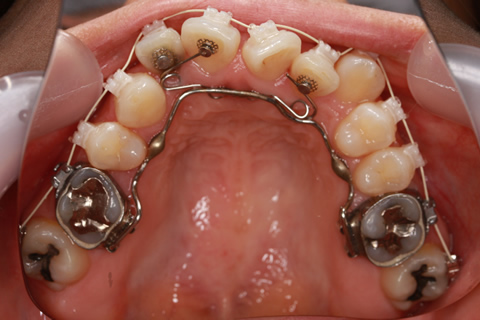

受け口(反対咬合)の症例

症例一覧